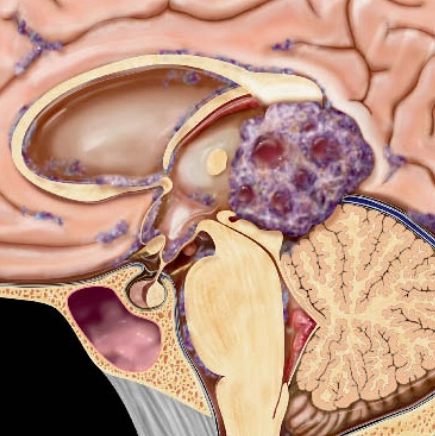

U nguyên bào mạch máu hệ thần kinh trung ương - Hemangioblastoma (central nervous system)